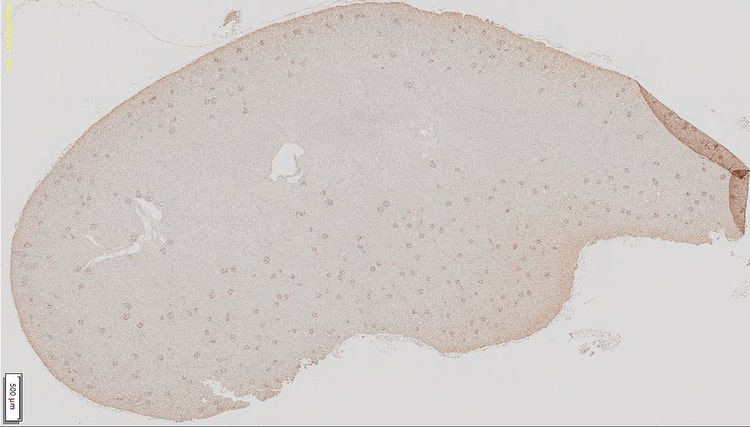

[Izq.] Portaobjetos con corte de tejido renal en 20x que muestra glomérulos teñidos de marrón oscuro. [Dcha.] Portaobjetos en 10x que muestra la detección basada en el método de valor umbral convencional (en rojo) y en donde no se distinguen las células glomerulares de las otras células tisulares.

El análisis de imágenes, provenientes de cortes de riñón, puede ser crucial para determinar cambios en la morfología o cantidad de los glomérulos. Sin embargo, procesar varias muestras en la investigación puede llevar mucho tiempo y ser subjetivo. Para acelerar y optimizar este proceso, los investigadores en nefropatología pueden usar el sistema de escaneo de portaobjetos digitales SLIDEVIEW VS200 con el fin de escanear rápidamente una gran cantidad de portaobjetos. El software de análisis de imágenes del sistema ahora integra un módulo de red neuronal por aprendizaje profundo, cuya formación permite reconocer los glomérulos aparte de las variaciones de tamaño, forma o color.